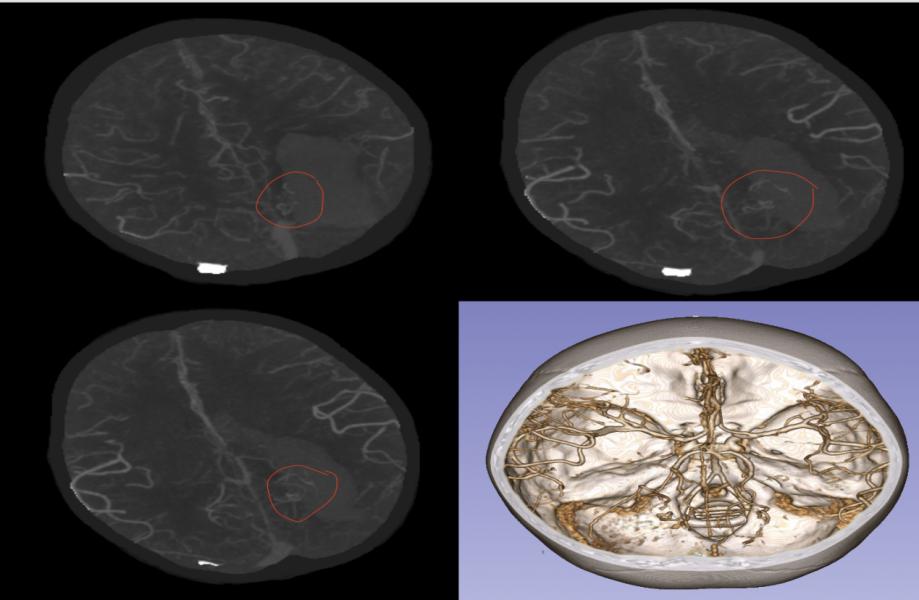

术后第十天复查见血肿吸收,水肿消退